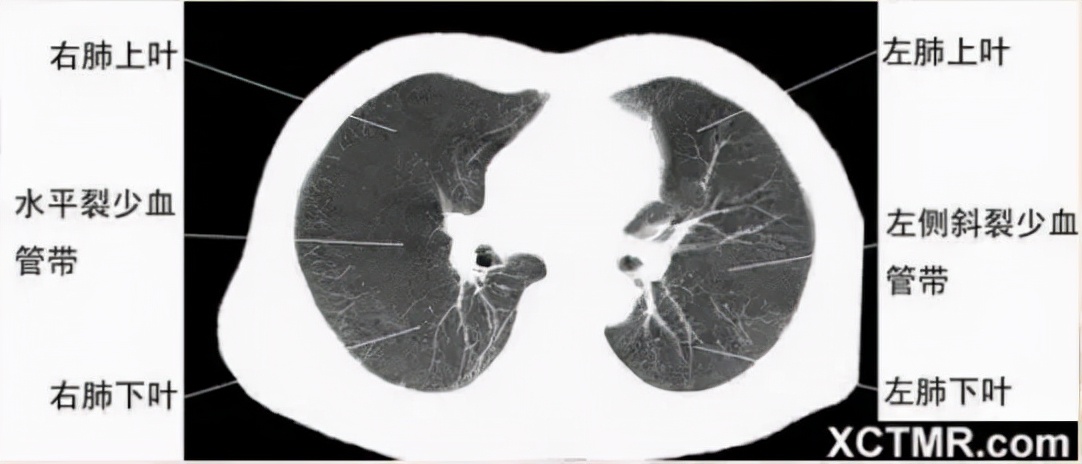

右上叶支气管层面